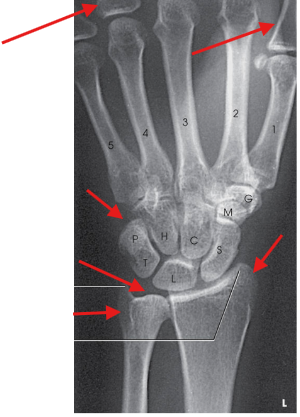

Distal radius and ulna, carpals, and proximal half of metacarpals

no excessive flexion of digits to overlap and obscure metacarpals

no rotation in carpals, metacarpals, radius, and ulna

open radioulnar joint space

45 degree rotation of anatomy

slight overlap of the distal radius and ulna

slight interosseous space between third, fourth, and fifth metacarpal bodies

trapezium and distal half of the scaphoid without superimposition